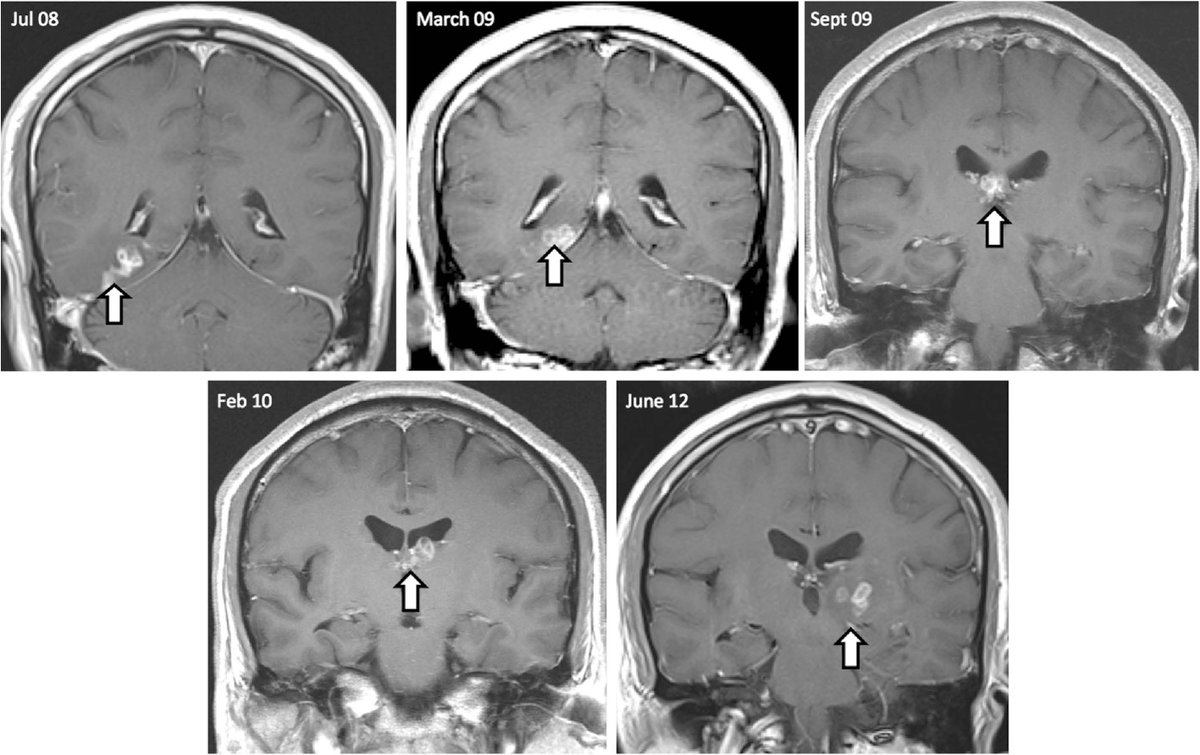

وجد علماء في سياق دراسة حالات أشخاص راشدين فقدوا نصف أدمغتهم كلياً في مرحلة الطفولة، أن النصف الثاني من الدماغ أعاد وصل أجزائه المتبقية ببعضها بعضا، مما ساعد الشخص المعني كما يبدو على مواصلة نشاطه كما لو كان دماغه كاملاً تماماً

الدراسة شملت 6 مشاركين بالغين كانوا قد خضعوا لعمليات استئصال نصف الكرة المخية في مرحلة الطفولة بغية الحد من نوبات صرع كانوا يعانون منها، بالإضافة إلى 6 مشاركين في مجموعة ضبط

ظن الباحثون أنهم سيكتشفون روابط أضعف داخل شبكات معينة لدى المشاركين الذين يملكون نصف كرة دماغية واحدة، لأن كثيراً من تلك الشبكات عادةً ما يشمل نصفي الكرة الدماغية لدى أشخاص يملكون أدمغة كاملة

لكن خلافاً لذلك، وجدوا لدى أولئك المشاركين تواصلاً شاملاً طبيعياً مدهشاً بين أجزاء الدماغ، فضلاً عن روابط بين الشبكات الدماغية المختلفة أقوى من تلك التي تمتعت بها مجموعة الضبط

وساعدت هذه التجربة في معرفة إلى أي مدى بإمكان الدماغ أن ينظم عملياته في حالات مختلفة عن بعضها بعضاً تماماً لمرضى استئصال نصف الكرة الدماغية، ما سيتيح فهم آليات الدماغ العامة بشكل أفضل